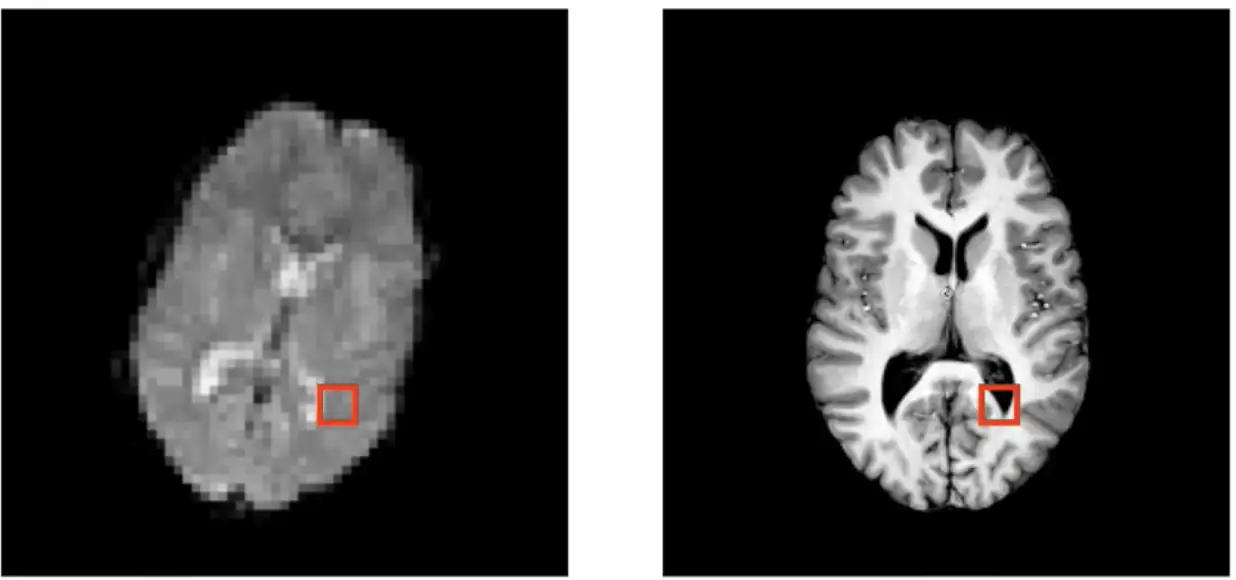

图像配准是将两幅或多幅图像对齐的过程,使其具有相同的几何参考系,从而便于比较、融合或分析。它广泛应用于医学影像、遥感、工业检测等领域。

图像配准是计算机视觉领域的一项基本技术,它旨在将两幅或多幅图像对齐,以便它们可以进行比较和分析。在本章中,我们将深入探讨图像配准的理论基础,包括其基本原理、算法分类和优缺点。